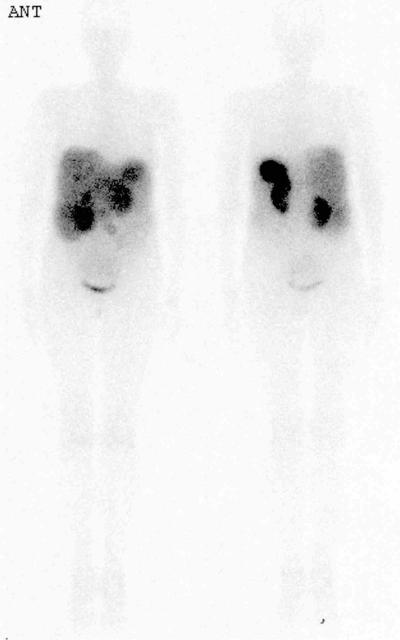

Octreotide Case 5

51 year old male. Previous resected appendiceal carcinoid. Ultrasound shows abnormal liver texture ?metastases. Urinary 5HIAA 2502 (normal 5-37), serum chromogranin A 10180 units / lProcedure

Anterior and posterior images are shown, 48hrs after injection